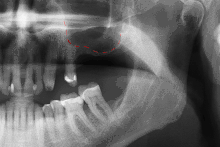

Before undergoing sinus augmentation, diagnostics are run to determine the health of the patient's sinuses. Panoramic radiographs are taken to map out the patient's upper jaw and sinuses. In special instances, cone beam computed tomography is preferable to measure the sinus's height and width, and to rule out any sinus disease or pathology.[5]